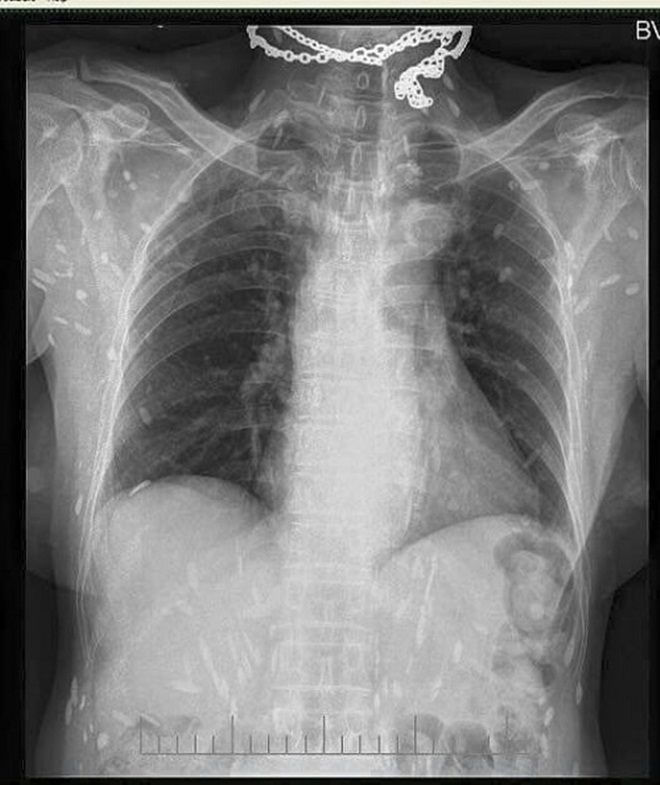

Trong những ngày qua, trên mạng xã hội chia sẻ rất rầm rộ về một hình ảnh chụp Xquang, kèm theo hình ảnh này là lời cảnh báo: “Hình ảnh được ghi nhận tại Bệnh viện đa khoa Trung ương Thái Nguyên.

Người gạo là có thật các bác ạ. Hình ảnh XQ trên là của bệnh nhân nhiễm sán xơ mít do ăn phải thức ăn sống (có thể là rau sống, tiết canh, gỏi cá…) có nhiễm trứng, ấu trùng sán…”.

Rất nhiều người khi quan sát hình ảnh này không khỏi hốt hoảng khi hình những nốt trắng được cho là sán sơ mít có ở khắp cơ thể. Thậm chí, có người còn bình luận: “Người nhiều sán thế này, có khi đứt tay máu không chảy mà sán lại chạy ra”.

Để có thông tin rõ hơn về mặt chuyên môn, chúng tôi đã chuyển hình ảnh này đến BS Trần Huy Thọ - Trưởng khoa Điều trị (Viện Sốt rét - Ký sinh trùng - Côn trùng Trung ương), thì được biết, viện cũng đã gặp nhiều trường hợp bị sán cơ, tuy nhiên nhìn hình ảnh như trên phim thì bản thân bác sĩ Thọ chưa gặp bao giờ.

“Nhiều khả năng đây là sán cơ, tuy nhiên để khẳng định chính xác thì tôi phải hỏi bệnh sử, có hồ sơ bệnh án, kết quả làm các xét nghiệm, thậm chí là cả địa phương nơi đó tập quán ăn uống như thế nào, nếu chỉ nhìn vào hình ảnh thì không thể khẳng định 100%”, BS Thọ cho hay.

Theo bác sĩ Thọ, trong trường hợp sán cơ nhiều như vậy, thì đó có thể là những nốt vôi hóa ở trong cơ. “Đây có thể là những nốt vôi hoá trong cơ, khi nang sán trong cơ thoái triển và thành vôi hoá”, BS Thọ cho biết.